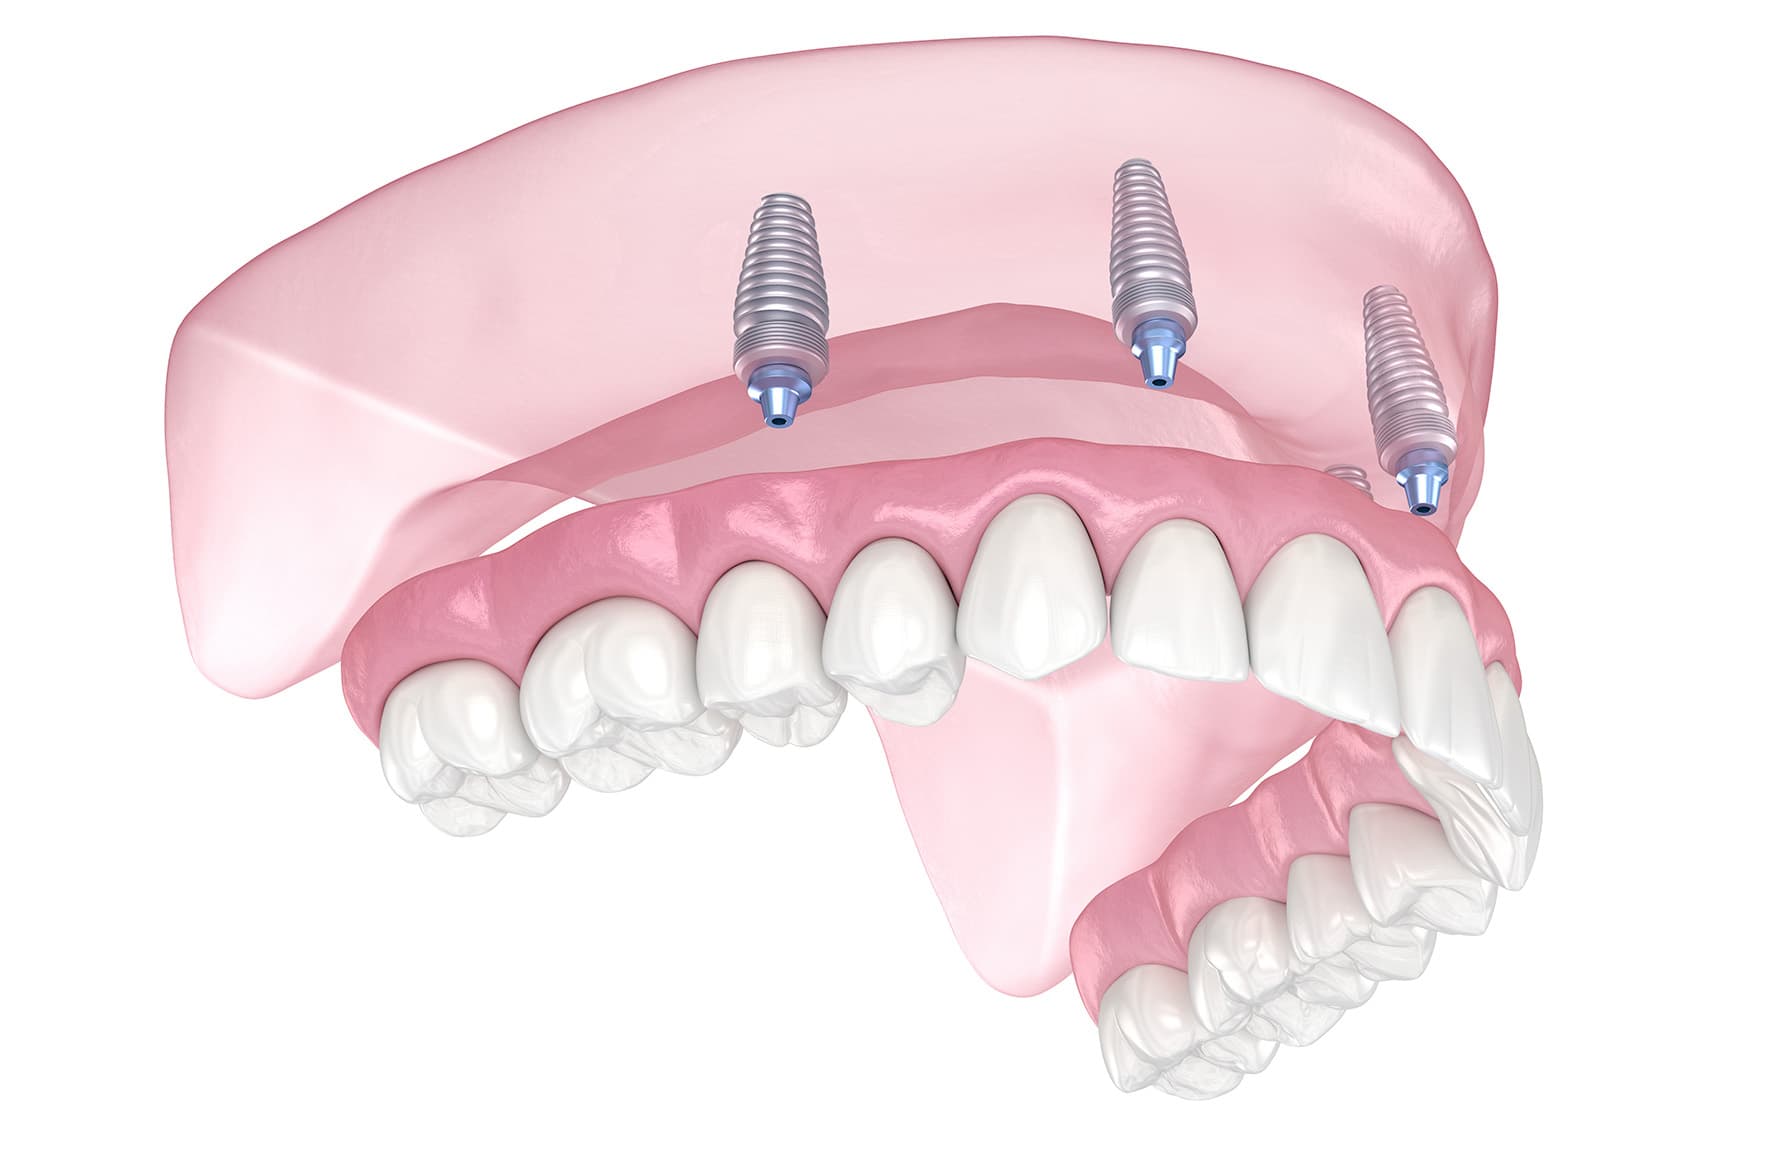

De vaste prothese wordt op 4 tot 6 implantaten (kunstwortel) in uw boven- en/of uw onderkaak bevestigd en zit muurvast. Hierbij wordt gebruik gemaakt van de all-on-4 of all-on-6 methode.

Bij deze methode wordt een compleet werkstuk (boog met tanden) vastgezet op slechts 4 of 6 implantaten. Doordat de twee achterste implantaten schuin naar achteren in uw kaak worden geplaatst, wordt er voldoende steun gecreëerd voor het complete werkstuk. Er wordt voor het plaatsen van de implantaten gebruik gemaakt van een digitale mal. Daardoor worden de implantaten zeer nauwkeurig geplaatst en hoeft uw tandvlees niet gehecht te worden. De kans op napijn is nihil.